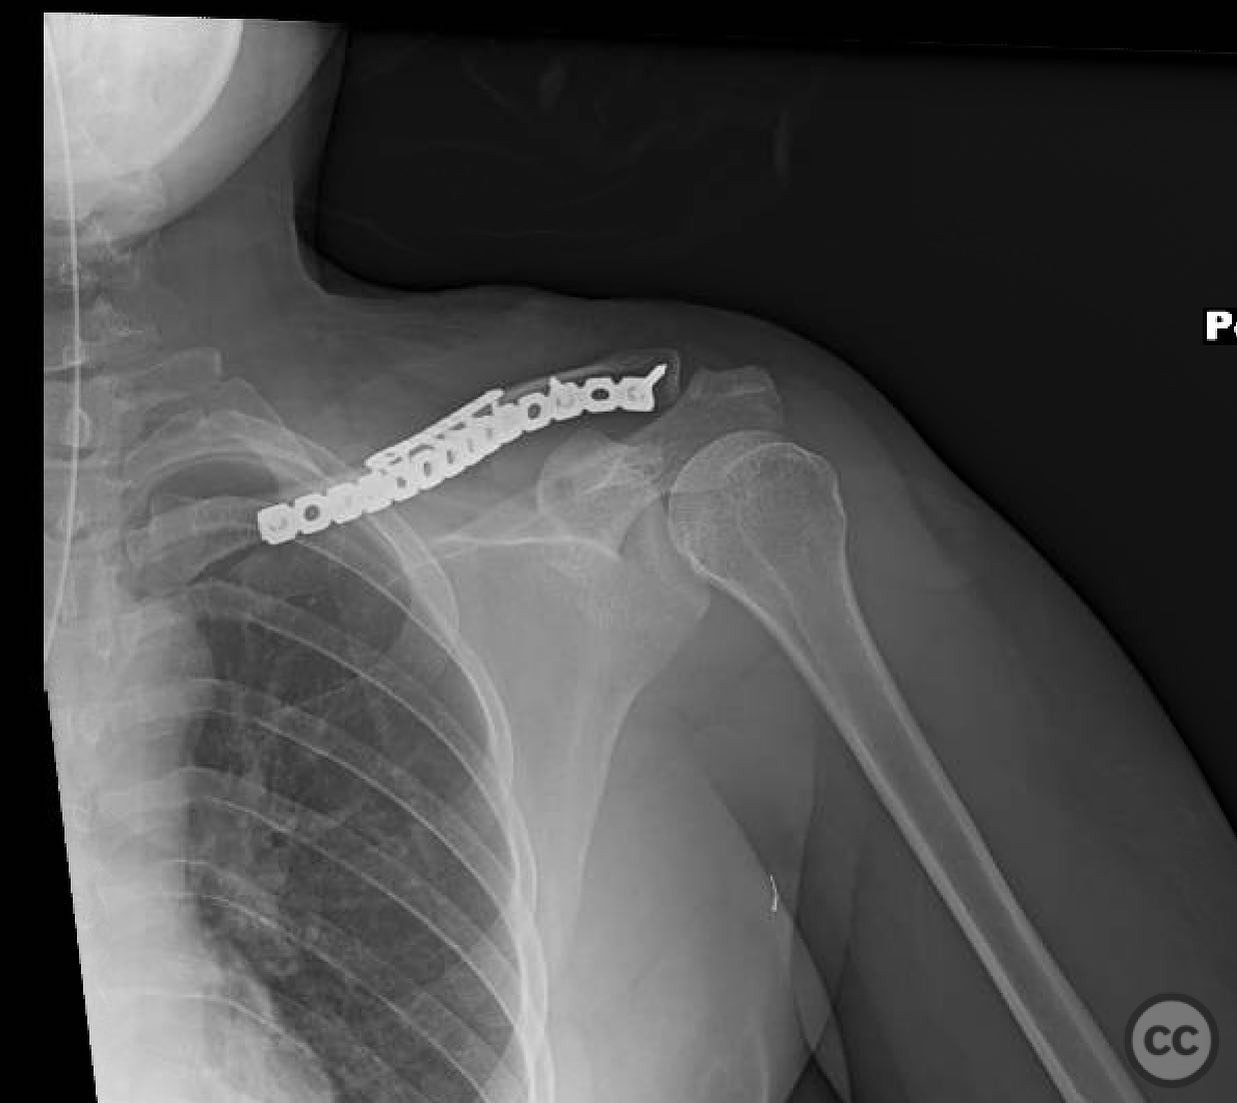

Open Diaphyseal Clavicle Fracture with Butterfly Fragments

Clinical and radiological findings:  A 35-year-old male presented with an open diaphyseal clavicle fracture following a high-energy motorcycle accident. The fracture was classified as a simple diaphyseal pattern with two butterfly fragments, according to the AO/OTA classification system, specifically 15-B2. The patient exhibited significant soft tissue injury but no neurovascular compromise. Initial radiographs confirmed the fracture pattern, and the wound was thoroughly irrigated and debrided in the emergency department.

Planning remarks:  The preoperative plan involved direct exposure of the fracture site with anatomic clamp reduction. Interfragmentary compression was planned using lag screws for the butterfly fragments, followed by application of a reconstruction plate on the anterior inferior aspect of the clavicle for neutralization.

During the procedure, anatomic reduction of the butterfly fragments was achieved using 2.4mm lag screws for interfragmentary compression. The main segment reduction proved challenging due to instability; hence, a 2.4mm "clamp replacement plate" was temporarily used to maintain reduction. A reconstruction plate was contoured and applied to the anterior inferior clavicle, providing a neutralization construct. Absolute stability was achieved, anticipating primary bone healing.

Orthopaedic implants used:   2.4mm lag screws, 2.4mm clamp replacement plate, reconstruction plate.